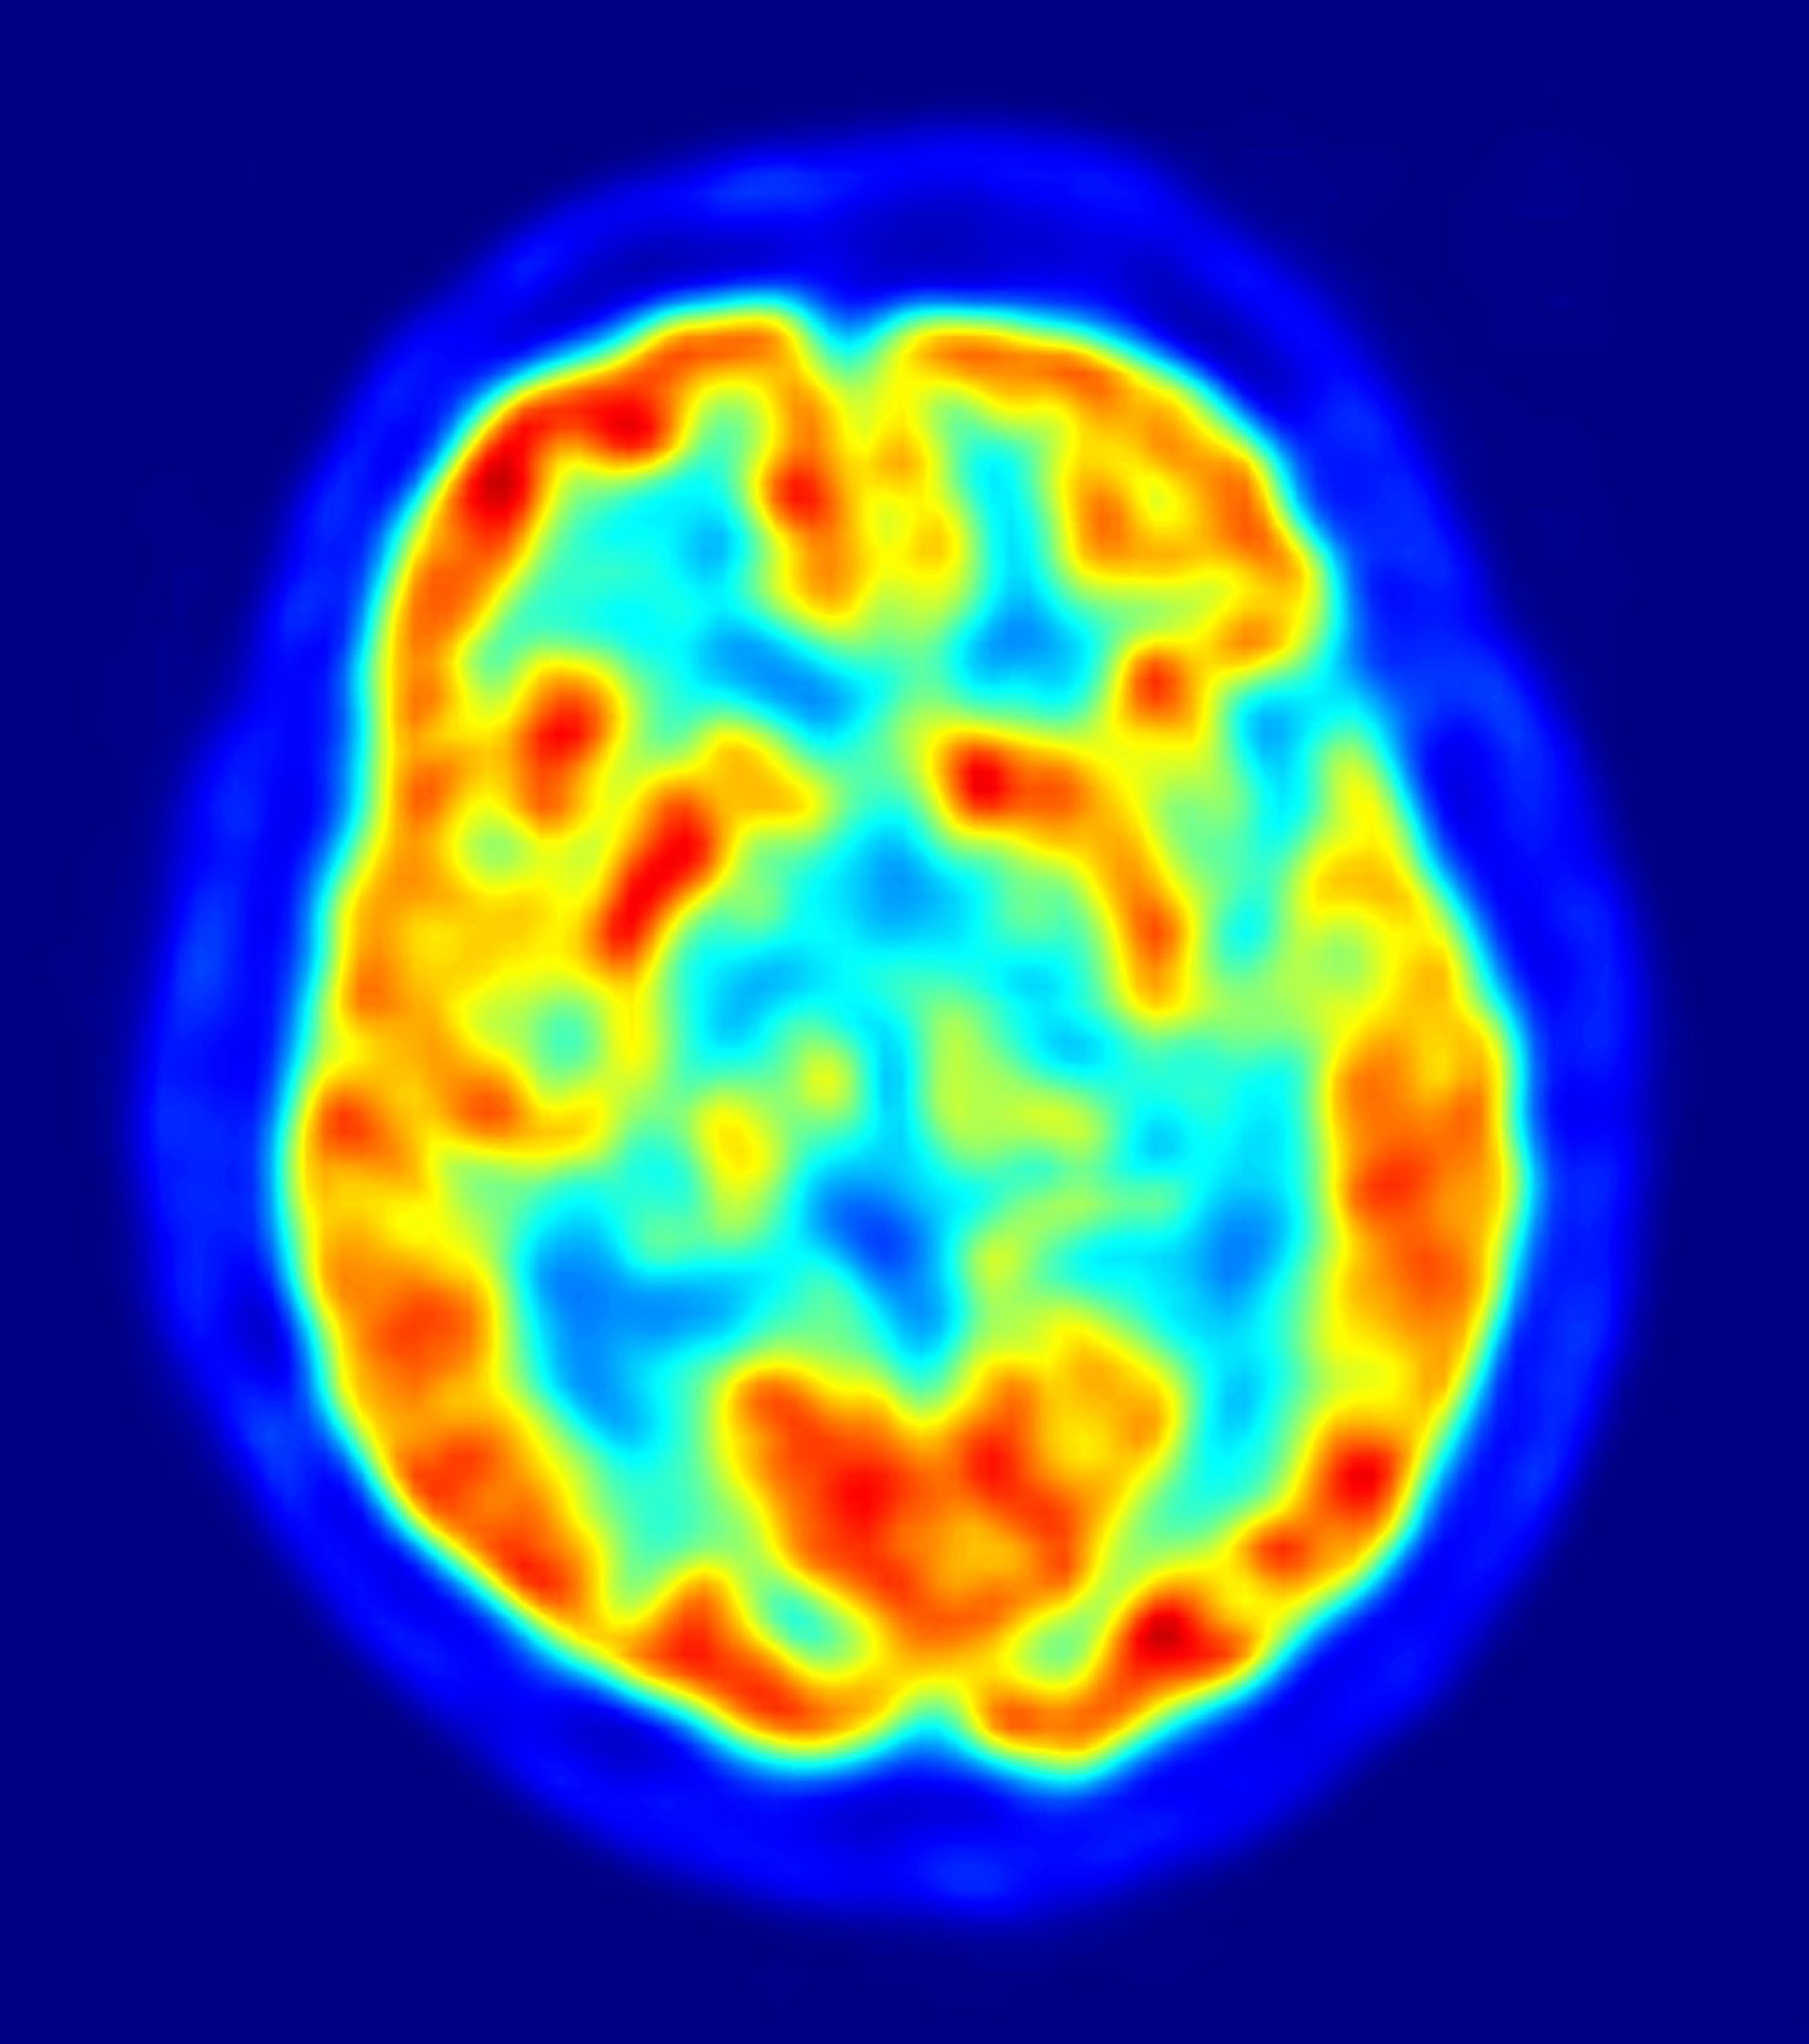

Entonces, los investigadores escanearon el cerebro de los voluntarios utilizando imagen por resonancia magnética funcional (fMRI, por sus siglas en inglés) mientras veían caras con expresiones de enfado, tristeza y neutralidad.

Así fueron capaces de medir cómo las diferentes regiones del cerebro reaccionaban y se comunicaban con otras cuando los voluntarios observaban caras de enfado, en contraposición a cuando lo que veían eran rostros tristes o neutrales.

Los resultados mostraron que los niveles bajos de serotonina hacen que la comunicación entre regiones específicas del cerebro del sistema límbico emocional --una estructura denominada amígdala-- y los lóbulos frontales más débil que cuando los niveles de serotonina son normales.